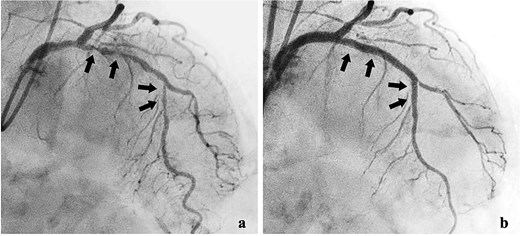

She was transferred to the catheterization laboratory, where coronary and lower extremity angiography revealed 90% stenosis of the left anterior descending artery and tumour blood supply via branches of the deep femoral artery (Figs 2a and 3a).

Lower extremity angiography. (a) Pre-embolization angiography showing tumour blush in the femur. (b) Post-embolization angiography showing tumour devascularization.

After a multidisciplinary team (MDT) review, transcatheter arterial embolization was initially performed for the bone metastasis. The tumour received blood from two deep femoral artery branches, and embolization with gelatin sponges and coils achieved adequate devascularization (Fig. 2b).